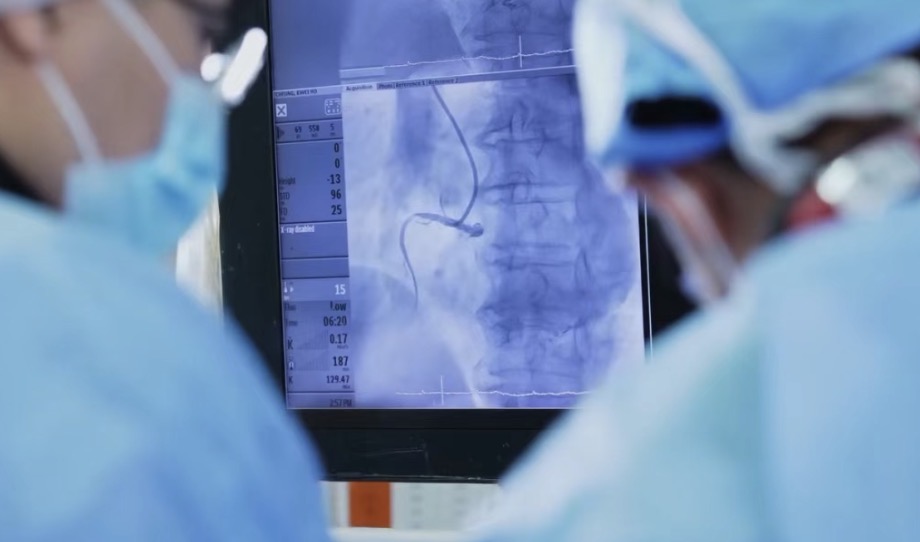

在近日举行的第十五届中国胸痛中心大会上,一份最新公布的《2025全国胸痛中心质控报告》披露了关于我国胸痛患者院内死亡率的一项关键数据。数据显示,我国胸痛中心急性心肌梗死患者院内死亡率自2021年以来持续下降,并于2025年首次降至3%以下,达到约2.9%。

《2025全国胸痛中心质控报告》由国家放射与治疗临床医学研究中心胸痛中心专家委员会发布,最新数据显示,2025年全国6000多家胸痛中心救治患者数量超过376万人,其中高危胸痛患者占比达40%,且近两年每年救治急性胸痛患者数量均超过300万人。

中国过去十余年间面临心血管疾病发病率和死亡率持续攀升的严峻形势,自2013年发布首版胸痛中心认证标准以来,已建成全球最大的胸痛中心网络,目前已覆盖全国绝大多数地区,急性心梗患者救治效率显著提升,关键救治指标持续改善。

上述报告的主要撰写者之一、中国人民解放军南部战区总医院向定成教授对第一财经记者表示:“胸痛中心救治患者数量再创新高,这主要归因得益于胸痛中心(包括胸痛救治单元及网点)急救网络覆盖范围的日益扩大、大众对胸痛中心认知度的逐渐提高。同时急性心肌梗死患者接受再灌注治疗的比例首次突破90%,说明更多的患者能够得到最有效的治疗。”

报告称,相比于自行来院,标准版胸痛中心呼叫120来院的心梗患者从发病到首次医疗接触的时间显著缩短;但目前呼叫120入院的比例仍仅在11%左右。“这说明在胸痛中心建设的过程中,需要继续普及急性胸痛快速拨打120,争取黄金救治120分钟的理念,提高民众发生急性胸痛时的呼救意识,为患者争取最佳治疗时机。”向定成表示。

另一方面,由于胸痛中心建设促进了胸痛患者救治流程优化,提升各级医疗机构救治能力,这不仅使胸痛患者得到更好治疗,也降低了患者经济的负担,减少了住院费用和住院时间,从而节约了医疗资源。数据显示,标准版胸痛中心单位心梗患者平均住院费用从2021年到2025年持续下降,已从约3万元下降到约2.5万元。

心血管疾病是全球人口过早死亡的主要原因之一,胸痛作为急性心血管疾病的最常见症状,其救治关键在于构建绿色通道,实现早发现、早治疗。中国胸痛中心的建设目标是通过院前急救与院内多学科联动,最大限度缩短救治时间、降低死亡率、改善预后,减轻疾病负担。